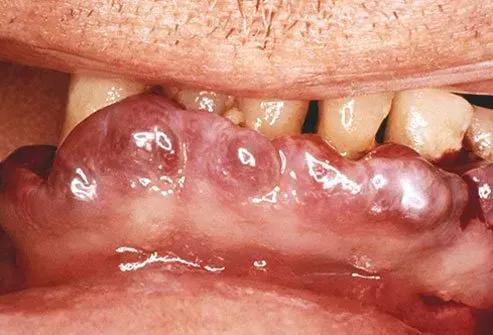

Lebbra

Lebbra is a disease reported in ancient times in places like Egypt China and India. It is caused by slow-growing bacteria that can form growths skin discolorations and nerve damage. It may lead to numbness disfigurements and blindness. But despite the development of a cure leprosy hasn't disappeared. Today more than 200000 new cases are reported each year and five countries report 80% of new leprosy cases: India Indonesia Myanmar Brazil and Nigeria.